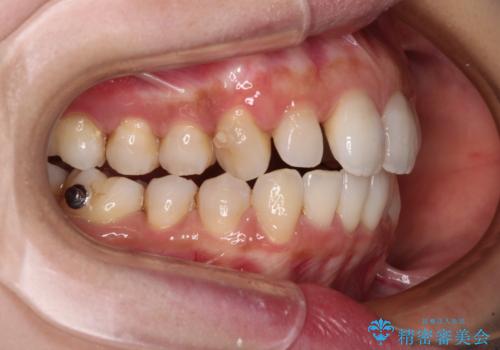

- デコボコと飛び出している前歯を気にして来院された患者様です。

歯列としてはインビザラインでもワイヤー矯正でも対応できるものでしたが、奥歯の咬み合わせを見た時に上顎がやや前方にあり、インビザライン単独では時間のかかってしまう可能性があるため、補助装置を治療当初に使用することで、インビザラインによる治療をスムーズに行えるように計画しました。